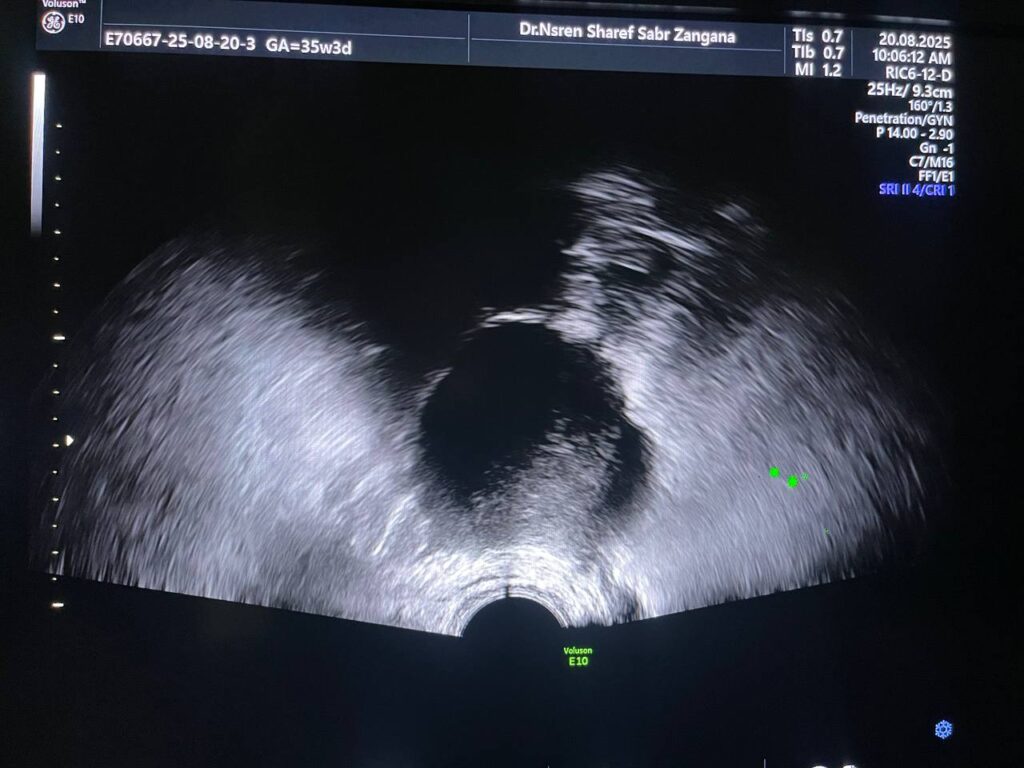

Right ovarian indistinct margin mass 50x52mm, still contain solid nodule size 24x29mm, associated with mild ascites , no significant prognosis seen as compare with previous scan size .

· Left ovary contain thin wall avascular circumscribed cystic mass size 37x26mm